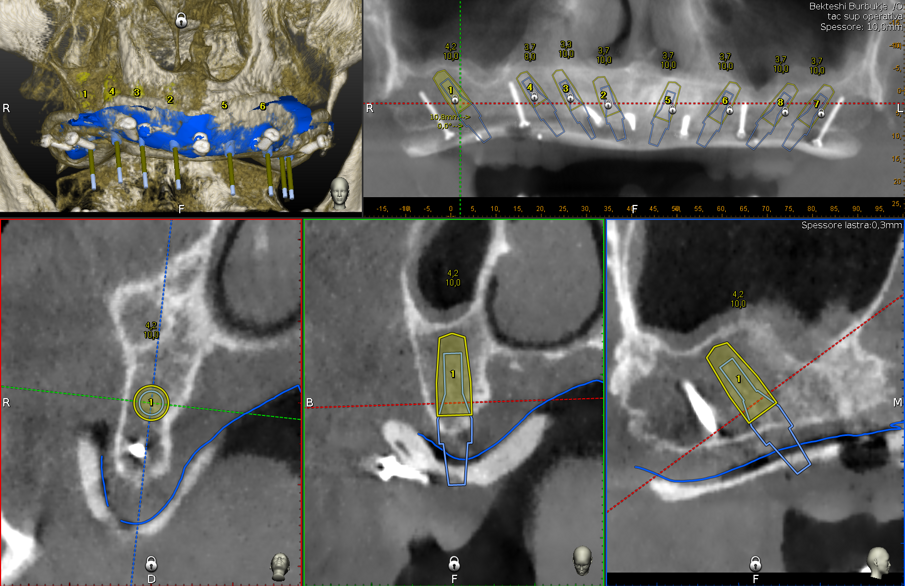

Inoltre l’aiuto della chirurgia navigata, consente di posizionare gli impianti in una posizione pianificata in precedenza ben distribuita lungo l’arcata, limitando al massimo i disparallelismi e semplificando le fasi protesiche.

Gli impianti vengono distribuiti lungo tutta l’arcata cercando il parallelismo e limitando il più possibile i cantilever (6-7 impianti superiori e 5-6 impianti inferiori). La scelta di utilizzare i monconi dritti (grazie al parallelismo degli impianti) è da preferire in quanto quest’ultimi sono anche i più robusti e resistenti nel tempo al carico assiale; inoltre caricano l’impianto lungo il suo asse limitando i carichi disassati. Una volta elevato il lembo mucoperiosteo ed evidenziato l’osso alveolare o basale, attenzione deve essere fatta nel fare un’ostectomia riduttiva mediante una fresa a palla del diametro di 0,6-0,8 cm per creare un piano più uniforme possibile tale da formare una piattaforma d’osso alla stessa altezza, guadagnando anche spessore V-L ed uniformità. Gli impianti devono essere posizionati alla stessa altezza tra di loro e distanziati in maniera tale da favorire le manovre di igiene orale inter-implantare. Una volta posizionate le fixture sottocrestali (1-3 mm) come descritto, vanno connessi i monconi solitamente con collare mucoso di 3-4,5 mm in altezza, ponendo particolare attenzione che i tessuti molli suturati non coprano la parte di accoppiamento conometrico. Verificato il parallelismo corretto dei monconi mediante i pin parallelizzatori, siamo certi che l’accoppiamento e la disconnessione delle cappette contenute nella protesi potrà avvenire nel miglior modo possibile senza creare tensioni.